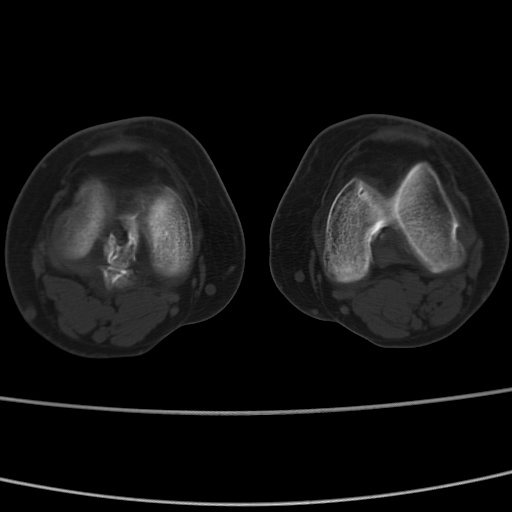

女性,50岁。【请提供患者临床症状体征】

右膝关节退行性改变,关节游离鼠。

右膝关节退行性改变,滑膜黏液囊钙/骨化并游离。

右膝关节退行性改变